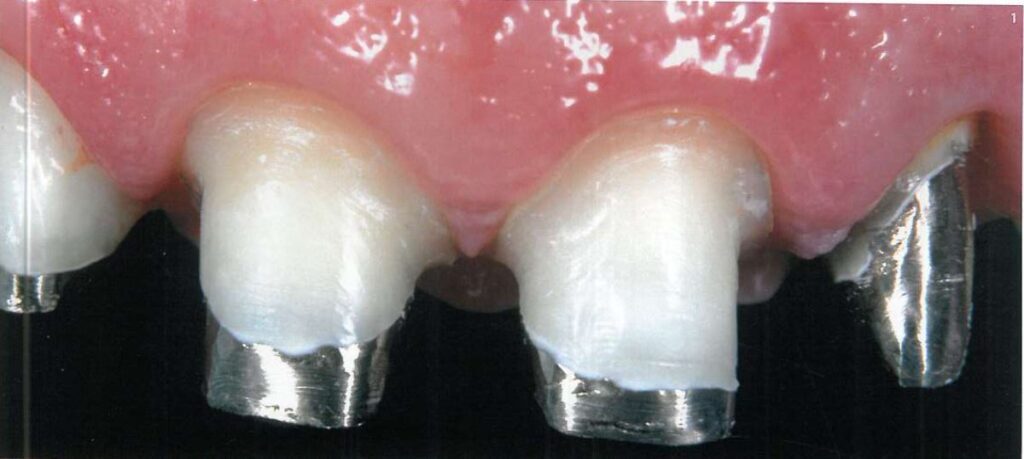

Lấy dấu yêu cầu phải ghi lại chính xác kích thước cùi răng, vị trí mô mềm, đặc biệt là hình dạng đường hoàn tất và mối tương quan giữa cùi răng với các răng kế cận trên cung hàm (H1).

Hình 9 mô tả vị trí lí tưởng của 2 sợi chỉ trong khe nướu, khi đó khe nướu rộng sang bên > 0.5 mm và tách xuống dưới > 0.5 mm để cho phép ghi dấu 1 phần mô răng lành bên dưới đường hoàn tất.